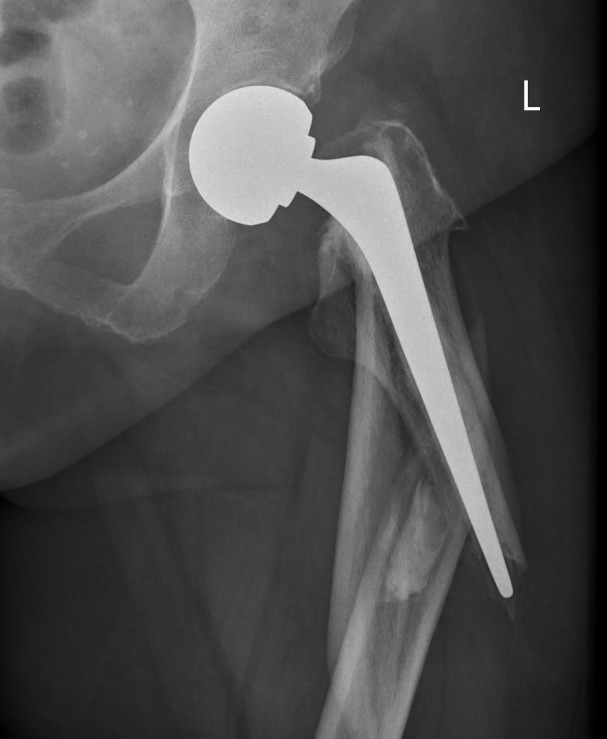

Long stem uncemented revision